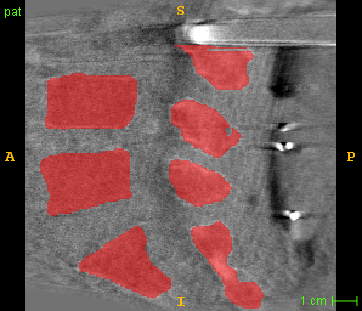

As the above network is designed for 2D images, it is difficult to keep inter-slice spatial continuity. As in Fig. 3(a), we design a 3D segmentation network. A 3D CBCT volume and a CT volume are first split to 2D images and , then the pre-trained A3DSegNet network serves as an online translator and generates synthetic images and . We recombine and to and by stacking them along the slice dimension. Finally, we use a low-quality 3D segmentor and a high-quality 3D segmentor to map a volume from image domain to shape domain:

Since the groundtruth segmentation of CBCT image is not available, we apply explicit shape constraints on CT segmentation and implicit shape constraints between raw and translated segmentation results (Fig. 3 (b)):

To further improve the segmentation performance, we introduce the 3D segmentation network as in Fig. 3. Our 3D model increases the Dice score from 0.819 to 0.926 and reduces the average ASD by 44% (from 1.47mm to 0.82mm). As shown in Fig. 7, the typical inter-slice discontinuous problem happening in 2D segmentation is fixed with our 3D model, which also runs over 100 times faster than slice-by slice 2D segmentation as measured on a PC with an Intel Xeon E5-2678 and a Nvidia GeForce GTX 2080 Ti.

2D Net

3D Net